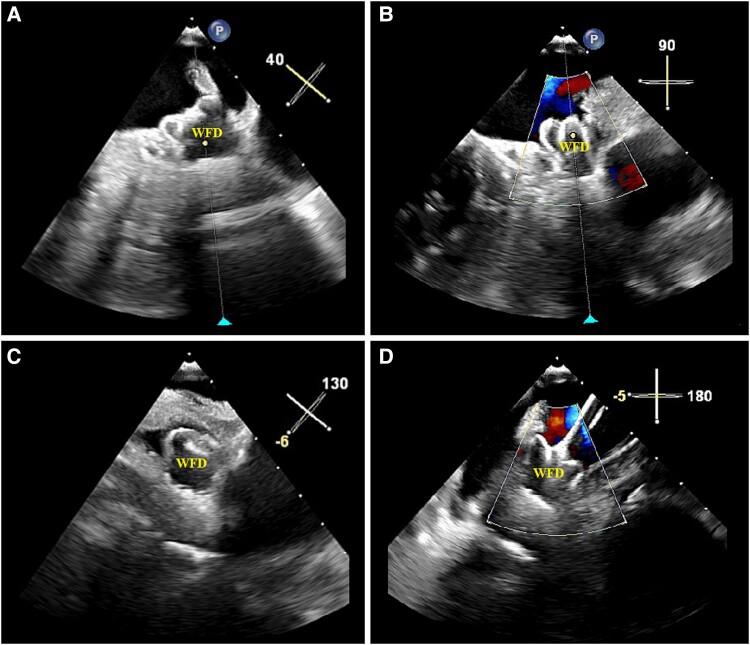

In patients with non-valvular atrial fibrillation, the vast majority of thrombi originate in the left atrial appendage (LAA). Thus, occluding the LAA significantly reduces one's risk for developing an ischaemic stroke. To date, many different surgical methodologies in LAA occlusion (LAAO)/exclusion have been studied and utilized. Unfortunately, patients are often left with incomplete closure of their LAA, leaving behind residual lobes that continue to allow thrombus formations. With the recent rise in percutaneous approaches and devices such as the WATCHMAN FLX, there have been proven success rates in achieving total closure of the LAA. Reports and investigations regarding the utilization of WATCHMAN FLX devices in patients with surgically incomplete LAAO remain limited.

We present three cases of patients who had previously undergone surgical exclusion of the LAA yet unfortunately were left with residual LAA that continued to place them at high risk for an ischaemic stroke. Percutaneous LAAO with the WATCHMAN FLX was utilized to successfully achieve complete sealing of the residual lobes in failed LAA surgical closures.

Our multicentre case series elucidates that an increased risk of stroke due to surgical LAAO failure is a real-world possibility that is likely to be encountered in clinical practice. We demonstrate in this series how the WATCHMAN FLX may provide a feasible and safe method to supplement a surgically incomplete LAAO to allow for improved ischaemic stroke and systemic embolization risk reduction.